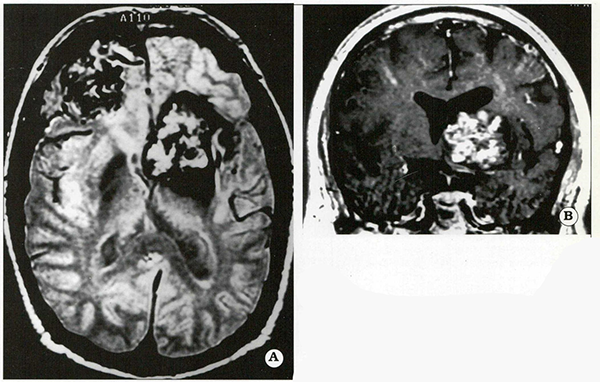

La elección del abordaje quirúrgico depende de la localización de la lesión, Es importante efectuar cuidadosamente un plan quirúrgico que permita un abordaje apropiado con mínima morbilidad. Las lesiones de la superficie anterolateral de los pedúnculos cerebrales (Fig, 2) y región de la cisterna interpeduncular pueden ser abordadas a través de un abordaje pterional transilviano o subtemporal, En contraposición, lesiones más inferiores ubicadas en la superficie anterolateral de la protuberancia anular son difíciles de abordar por la vía subtemporal clásica (Fig. 3), El uso de abordajes de base de cráneo, como por ejemplo el abordaje subtemporal transpetroso posterior, presigmoideoretrolaberíntico, transigmoideo, o sus combinaciones, permite una exposición más apropiada a esta región anatómica. Estos abordajes se efectúan con el paciente en posición supina, con un rollo por debajo del hombro y la cabeza rotada hacia el lado opuesto a la lesión, La elección y agresividad de estos abordajes debe basarse en el tamaño y características particulares de cada caso. Las lesiones ubicadas en la región pineal, superficie dorsal de los pedúnculos cerebrales, velo medular superior y pedúnculos cerebelosos superiores pueden ser resecadas por vía infratentorial supracerebelosa. Este abordaje puede ser efectuado en posición prono, semisentado, o posición 3/4 prono.

Fig. 3.

Paciente masculino de 27 años que presentó una hemorragia subaguda, estupor, deterioro progresivo del nivel de conciencia y marcada hemiparesia derecha progresiva. La tomografía computada (A) y las imágenes por resonancia (B, C) demuestran un hematoma en la protuberancia anular con compresión del parénquima. Esta lesiónfue abordada mediante un abordaje retrolaberíntico, presigmoideo. En el período postoperatorio inmediato el nivel de conciencia y la hemiparesia mejoraron, Este paciente presentó una paresia facial marcada que mejoró en 6 semanas.